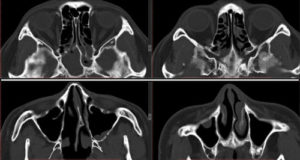

Рентгенография позволяет установить затемнение клиновидных пазух, что сигнализирует о скоплении в них гноя и наличии воспалительного процесса.

В тех случаях, когда эти два метода диагностики оказываются малоинформативными (в связи с индивидуальными особенностями строения пазух или течения заболевания), назначается компьютерная томография или МРТ, которые с высокой точностью выявляют патологии в придаточных пазухах носа.

КТ — исследование пазухи с помощью рентгеновского излучения. КТ позволяет выявить аномалии синуса, степень поражения слизистой. При исследовании с помощью КТ определяется уровень гноя в пазухе.